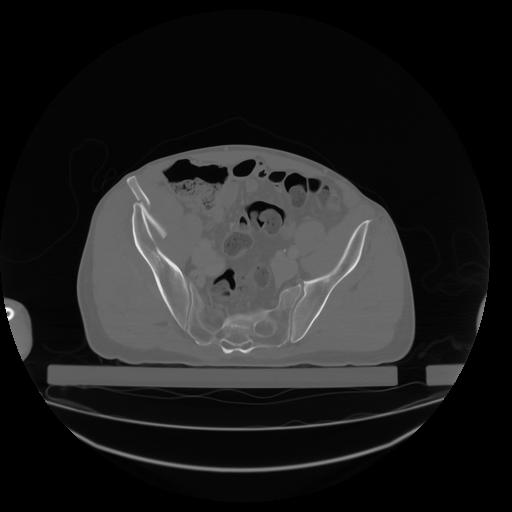

27 CUERPO,CE,Axial,3.0,CUERPO,,